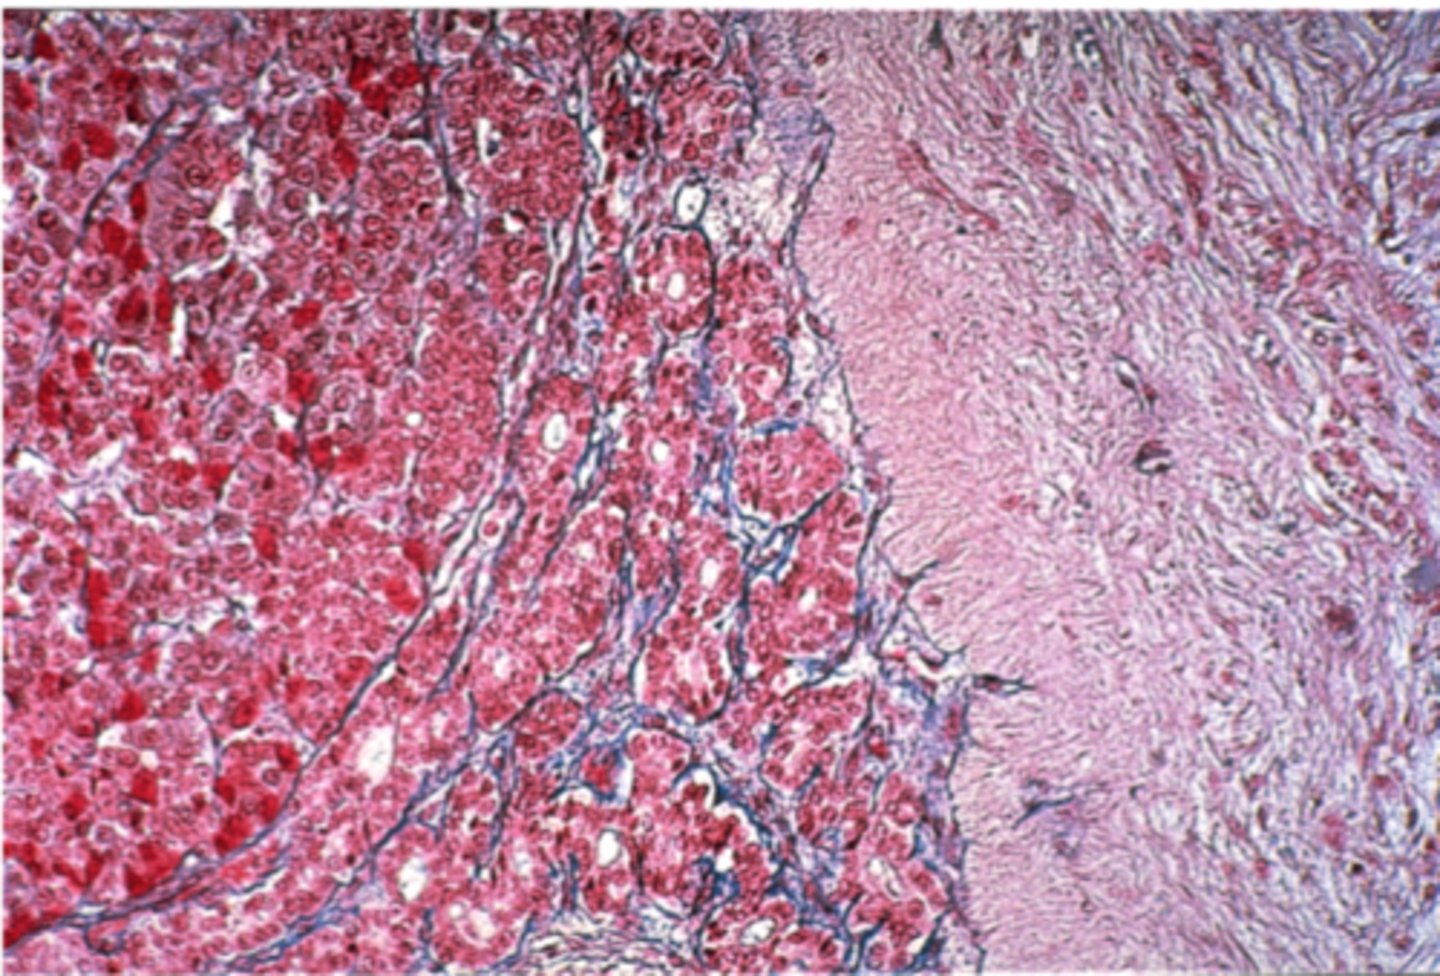

Liver

What is this?